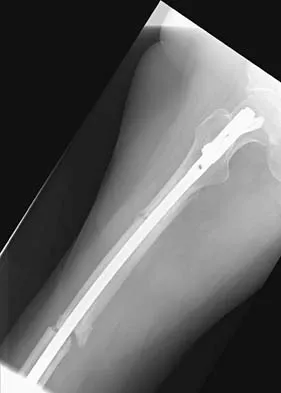

A 64-year-old man with a history of metastatic lung cancer reports increasing right hip pain over the period of several months. Radiographs are shown in Figures 3a and 3b. Initial management should consist of

Explanation

The patient has lung cancer metastatic to the right proximal femur. The lesion is large, has destroyed a portion of the cortex, and involves the peritrochanteric region. All of these findings put the patient at high risk for pathologic fracture. The lesion is amenable to intramedullary fixation in the form of some type of reconstruction nail. Chemotherapy alone will not restore the bone stock. Given the extent of the lesion, radiation therapy, chemotherapy, or embolization will not prevent fracture. A proximal femoral replacement would be indicated in patients with bone destruction extending into the femoral head and neck. Bisphosphonates may diminish the risk of subsequent lesions but are not sufficient to treat this high-risk lesion. Radiation therapy should be given postoperatively to prevent further bone destruction.